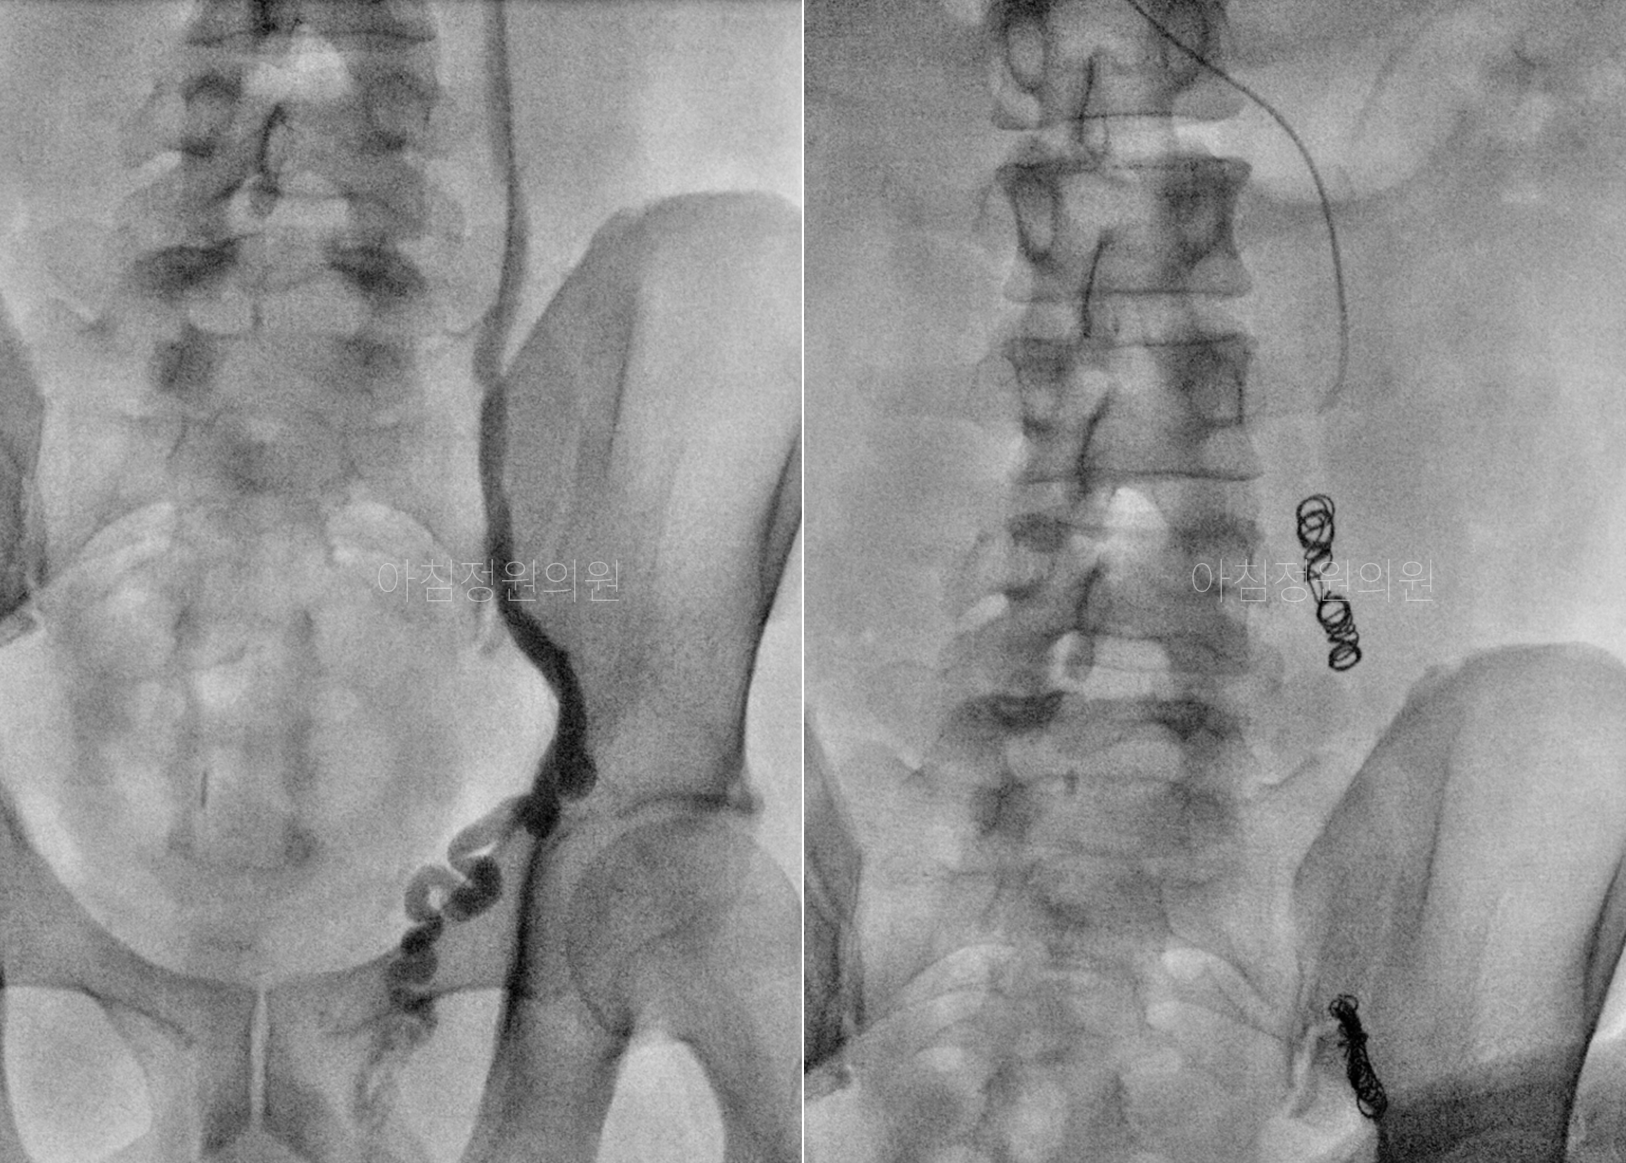

비수술적 치료, 정계정맥류 색전술

팔에 카테터를 삽입하여 문제 혈관까지 도달시킨 후,

색전물질을 주입하여 혈류를 차단하는 시술

색전물질인 백금 코일과 경화제를 이용하여

정맥류를 유발하는 문제 혈관을 막아주면,

이 곳으로 더이상 혈액이 흐르지 않게 됩니다.

차단된 혈관은 6개월에서 1년 사이에

서서히 몸으로 흡수되며, 자연스럽게 사라지게 됩니다.